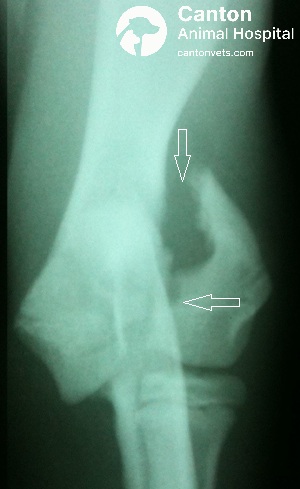

Radiographs (X-rays): Essential to visualize the fracture and determine whether it is complete, displaced, or involves multiple fragments. Thoracic radiographs may also be taken to rule out chest trauma in cases involving a fall or vehicular accident.

Once the fracture site is adequately exposed, fibrin, clots, blood, and any interposed soft tissue are carefully removed to ensure optimal visualization and allow precise anatomic reduction of the articular surface.

A transcondylar hole is drilled beginning just cranial and ventral to the palpable lateral epicondylar crest.

The drill hole is tapped, and the lateral condylar fragment is over-drilled to create a gliding hole before placing a transcondylar lag screw.

In some cases, the lateral condylar fragment is outwardly rotated, and the gliding hole is drilled from the intercondylar fracture surface outward through the lateral side of the condyle for more accurate central placement.

After reducing the fracture, the medial condyle is drilled and tapped, and the lag screw is secured across the condyle.

To provide rotational stability, an anti-rotational Kirschner wire is driven from the lateral condyle and seated into the medial cortex of the distal humeral shaft.

The elbow joint is put through a full range of motion to confirm stability and ensure no crepitus is present.